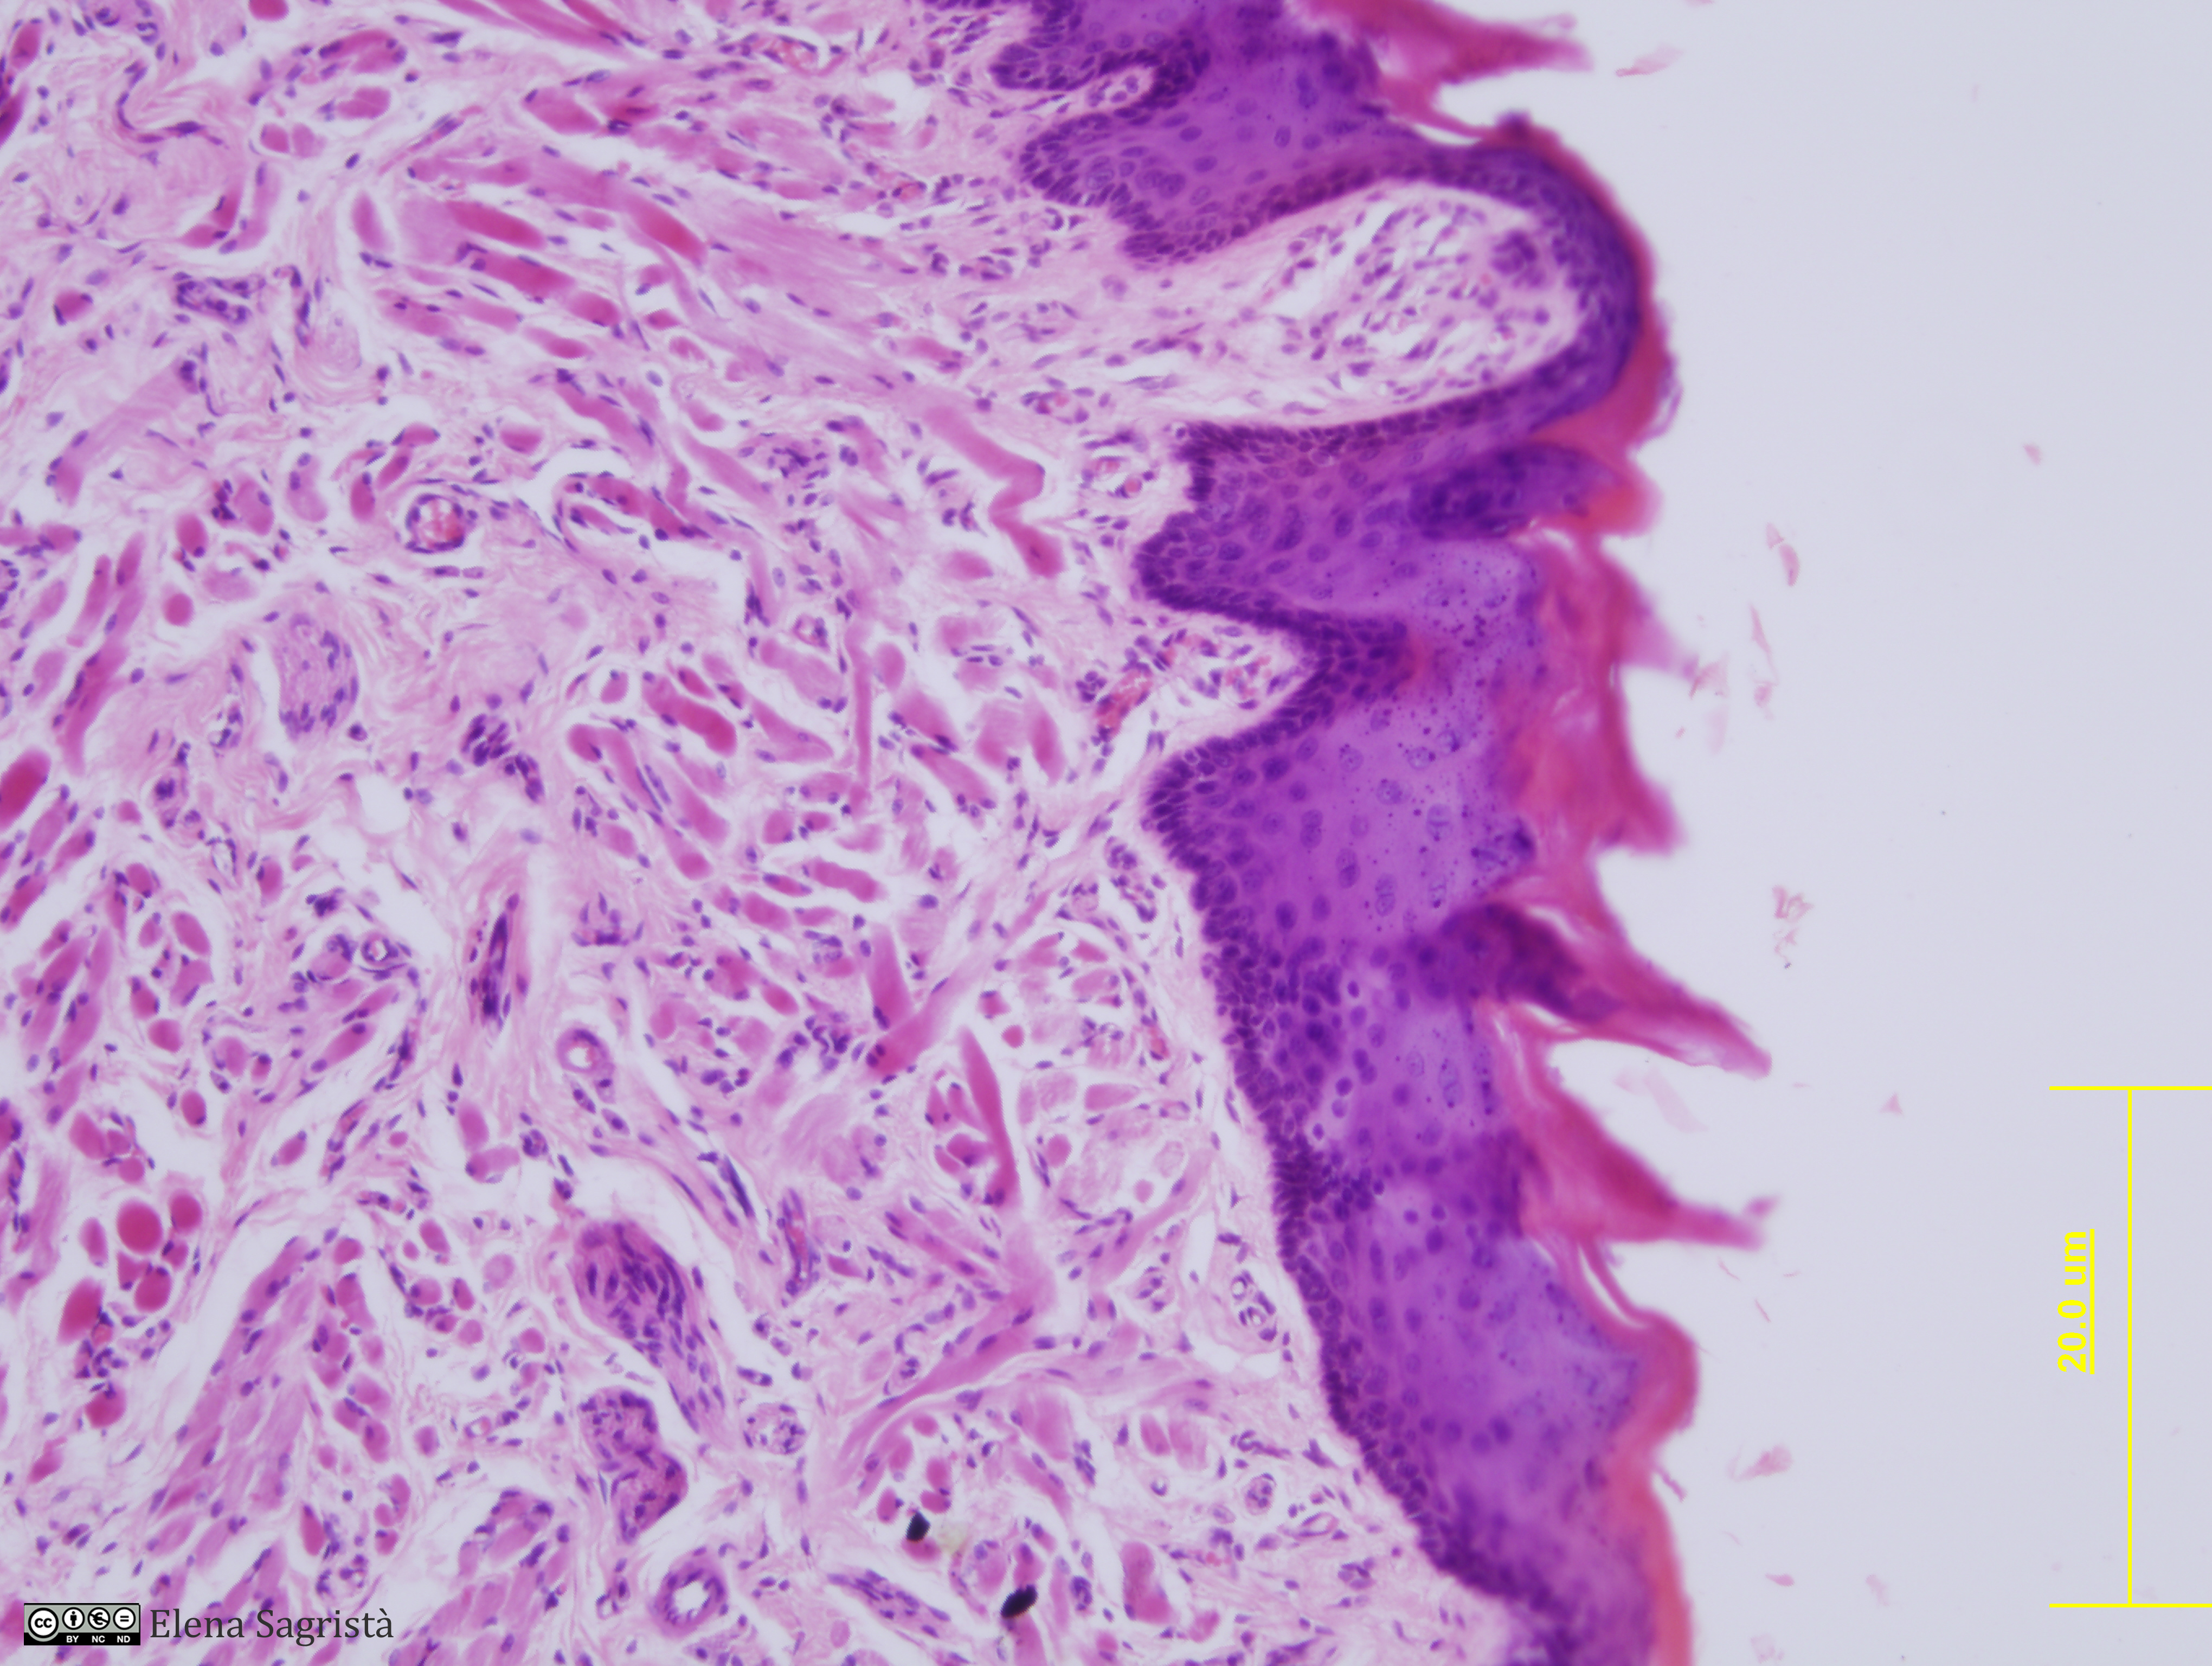

Histologia imatges: 14 Llengua

Imatges de preparacions histològiques de Llengua. Microscopia òptica.